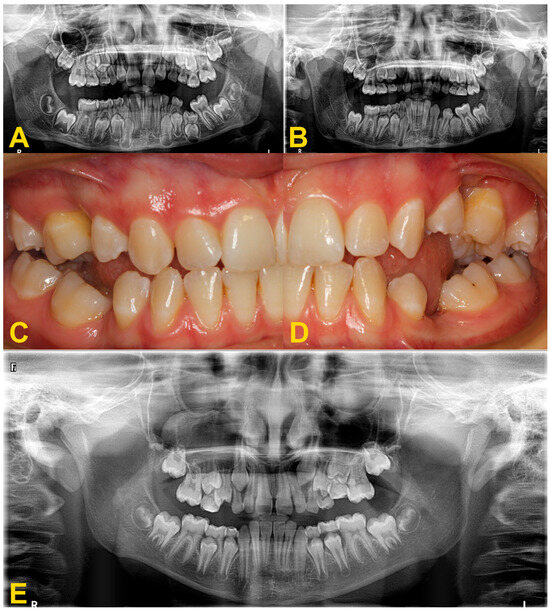

Figure 10.

Disorders of the occlusal plane and displacement of the adjacent teeth: (A,B) panoramic X-rays—displacement of the adjacent teeth, bone defect and growth delay of the permanent successor due to the severe infraocclusion of tooth no. 75 before (A) and after the extraction of tooth no. 75 (B). Surgery was performed under general anesthesia with simultaneous extraction of teeth nos. 38 and 48 due to crowding. Lack of space for tooth no. 35, improvement of root development and position of tooth no. 35; (C,D) intraoral photography (another patient)—displacement of the adjacent teeth, disturbance of the occlusal plane with lateral open bite, and bone defect—situation after too-late removal of reincluded teeth with lack of permanent successors, (E) panoramic X-ray—moderate infraocclusion of tooth no. 65, displacement of the tooth no. 25 in relation to its antimere, incorrect position of the tooth no. 23 with suspected cyst, moderate infraocclusion of teeth nos. 74, 84, and 85, no resorption of the mesial root of tooth no. 85, mild infraocclusion of tooth no. 75.

Maintaining a deciduous molar in patients with agenesis of the premolar successor is a reasonable treatment option. Clinical monitoring is required to evaluate mobility and the progression of infraocclusion. This should be associated with radiographic examination every 6 months to assess root resorption [29,30]. However, infraocclusion could cause reduced vertical growth in the area. In case of the absence of a permanent tooth germ, the tooth with progressive infraocclusion should be removed before a significant vertical disturbance of the occlusal plane occurs and a defect in the alveolar bone develops (Figure 10) [28,31]. Bone loss resulting from the extraction leads to less serious disorders than the possible defect due to progression of infraocclusion. Some authors suggest considering extraction of deciduous teeth without successors and showing infraocclusion of more than 2–3 mm before the growth spurt [27]. If it is necessary to use the tooth as an anchorage in orthodontic treatment, it is reasonably justified to postpone the extraction if it necessary to use the tooth as an anchorage in orthodontic treatment (Figure 9) [4,22]. During the orthodontic treatment, closing the space or replacing the missing tooth should be considered. The type of procedure depends on the amount of space in the arch, occlusal relationships, the profile, and the patient’s individual growth pattern [4,5,15,32].